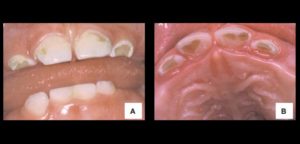

En 1978 La Academia Americana de Odontopediatría introdujo el término “Nursing Bottle Caries” para definir una forma severa de caries asociada al uso prolongado del